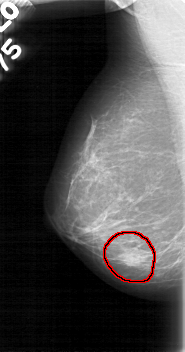

D_4017_1.RIGHT_MLO

RIGHT_MLO LINES 5266 PIXELS_PER_LINE 2761 BITS_PER_PIXEL 12 RESOLUTION 43.5 OVERLAY

FILE: D_4017_1.RIGHT_MLO.OVERLAY

TOTAL_ABNORMALITIES 1

ABNORMALITY 1

LESION_TYPE MASS SHAPE OVAL MARGINS OBSCURED

ASSESSMENT 0

SUBTLETY 3

PATHOLOGY BENIGN

TOTAL_OUTLINES 1

BOUNDARY